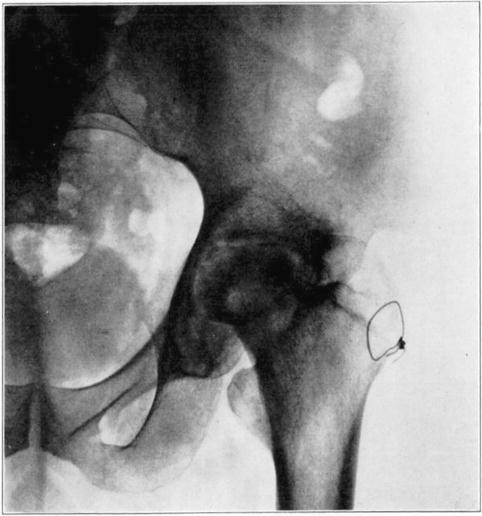

Operations which involve severence of bone or extensive separation of soft parts from bone may occasionally interfere with blood supply sufficiently to cause massive necrosis. An example of this is the necrosis of the head and neck of the femur in the following case in which arthroplasty of the hip was performed.

Case 1. Bony ankylosis following pyogenic arthritis.

Case 1. Twenty days after arthroplasty.

Case 1. Thirty-six days after arthroplasty. Beginning reduction in density in base of neck and shaft. No change in head.

Case 1. One hundred and fifty-one days after operation. Density of necrotic head unchanged but shaft and pelvis show atrophy of disuse.

Case 1. Two hundred and fifty days after operation. Head extensively reduced in density from invasion and replacement from the living bone of base of neck.

Case 1. Four hundred and four days postoperative Cavitation at base of head and further transformation.

The hip showed about forty degrees of flexion but marked limitation of abduction and rotation. Its strength had gradually improved and there was only slight discomfort in walking unless it was prolonged.

The cause for this exceptional occurrence of necrosis of head and neck without sequestration appeared to lie in the traumatism of head and denudation of neck of its covering of soft parts. However, it may have been due in part to deep-seated mild infection in the region of the new joint, despite the absence of discharge from that region. Failure of the necrotic head to be sequestrated speaks decidedly in favor of aseptic instead of septic necrosis although sequestration may not occur in the presence of mild infection of a necrotic area. In another case I observed necrosis of the head and neck following an arthroplasty in which there was infection of the wound with a purulent discharge, but the dead bone was sequestrated in the course of several weeks. In the case here reported functional stimulation of the bones resulting from movement of the joint, combined with protection of the necrotic head from weight-bearing, was followed by creeping substitution of the necrotic bone by new bone in the greater part of the head without either erosion of dead bone or the development of marked deformity.